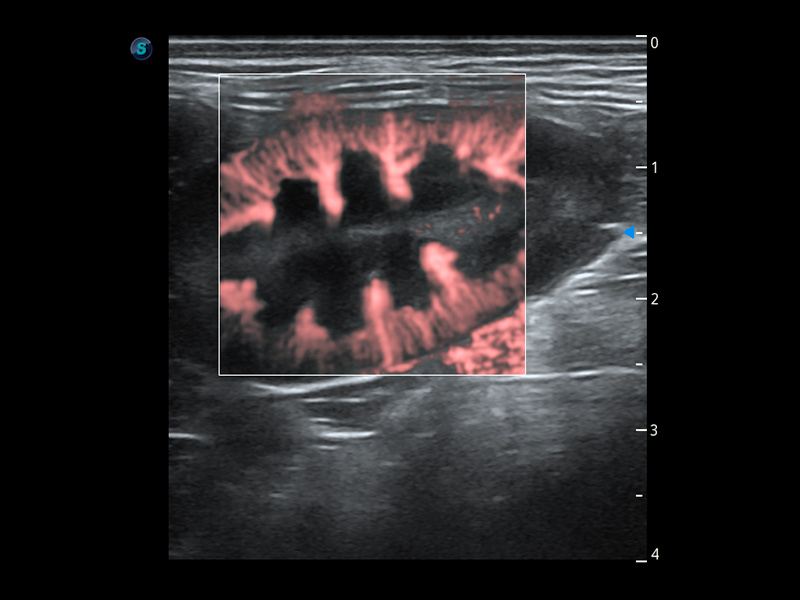

ProPet 60 作為一款高端臺(tái)式動(dòng)物超聲設(shè)備,為動(dòng)物醫(yī)生的日常診斷提供了一系列貼合動(dòng)物臨床需求、解決臨床實(shí)際問(wèn)題的高級(jí)成像功能。憑借全系列高清探頭,滿(mǎn)足醫(yī)生對(duì)腹部、心臟、生殖、淺表、肌骨等成像的所有需求,切實(shí)幫助您提升檢查效率,提高診斷信心。